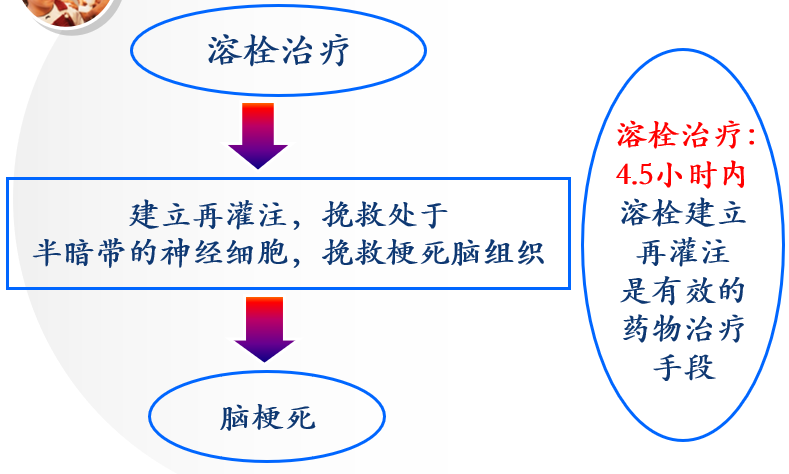

八、当头颅CT未见出血,可诊断未脑梗死

如为缺血性脑卒中,发病4.5小时内是静脉溶栓治疗的时间窗!!时间就是大脑!!

九、脑梗死静脉溶栓后该如何处理?脑梗死错过了时间窗,没赶上溶栓,如何处理?